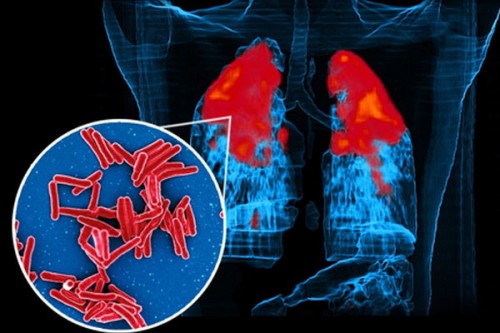

IIT Bombay study shows how TB bacteria shield themselves from antibiotics, stay alive longer

Technology | IANS | Published : Wed, Dec 03, 2025, 01:27 PM

AI-based diagnostic tools boosting TB, diabetes care: Government

Technology | IANS | Published : Sat, Dec 06, 2025, 11:59 AM